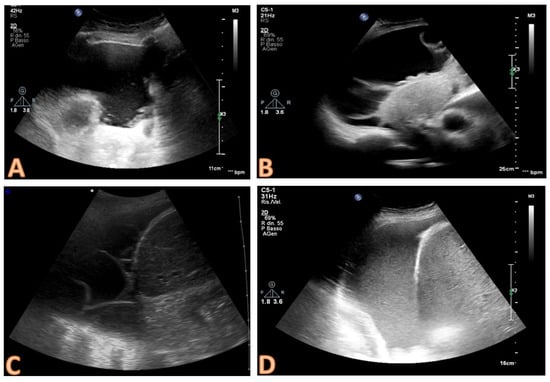

- anechoic (without echoic images);

- complex non-septated (echogenic material is detected inside the effusion);

- complex septated (floating fibrin strands or septs are found inside the effusions);

- homogenously echogenic.